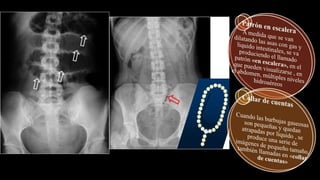

Obstrucción de intestino delgado

Ausencia de gas en el colón

Niveles hidroaéreos

Se concentran en el epigastrio

Se amontonan unas asas encimas de otras

en forma de escalera

Dilatación de asas de intestino delgado >2.5

cm proximales a la obstrucción

Busca el ciego no dilatado

Se amontonan unas asas encimas de otras en forma

de escalera

Dilatación de asas de intestino delgado >2.5 cm

proximales a la obstrucción